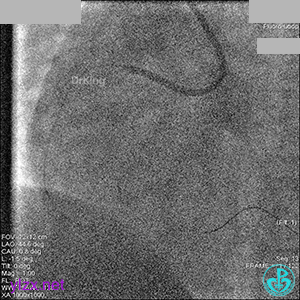

右冠脉血流3级,患者无症状,终止手术。

术后患者无特殊不适。